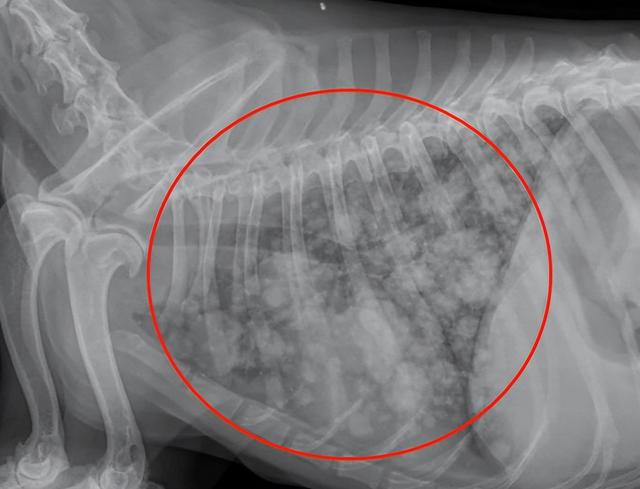

希望每个主人带狗狗检查时不要呈现这样的照片!下面这张图就是乳腺癌肺部转移X光照片。